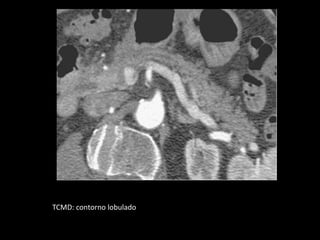

TCMD: contorno lobulado

O pâncreas não tem cápsula fibrosa e seu contorno

pode ser regular ou lobulado.